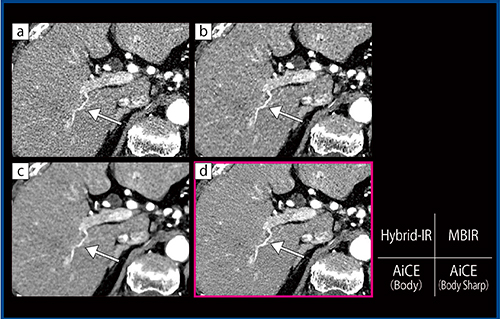

囊胞性病変である分枝型膵管内乳頭粘液性腫瘍(IPMN)症例(50歳代,男性:図3)においても,AiCE(Body Sharp)(d)はAiCE(Body)(c)に比べてノイズは少し増えているが,囊胞性病変の境界(→)は明瞭になっている。

図3 分枝型IPMN症例(50歳代,男性)の膵実質相